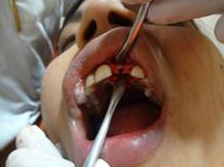

Pre Operation

Placement of Bone Grafting

Punch Cut

Use of Bone Graft & GTR membrane for an Implant